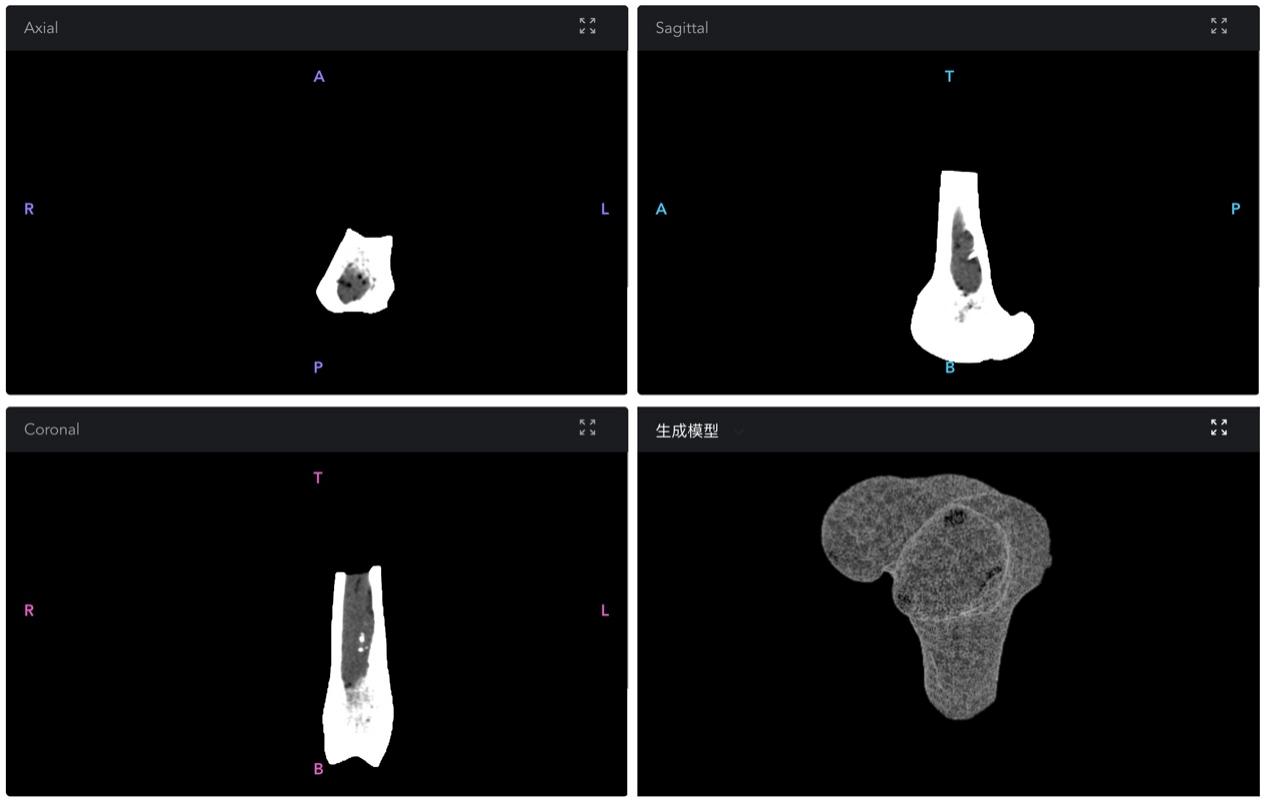

图1 缺损部位镜像CT影像切片及智能设计结果可视化展示

该团队综合运用深度学习、强化学习等人工智能技术,完成从患者临床CT影像,到定制化生成骨植入器械3D打印模型的端到端工作流创建,大大缩减了个性化假体骨设计的时间和成本,为骨缺损患者,特别是重大创伤后造成骨缺损,以及骨再生能力较弱,急需救治手术的患者群体提供了全新的医疗解决方案和思路。主要突破进展体现在以下三方面: